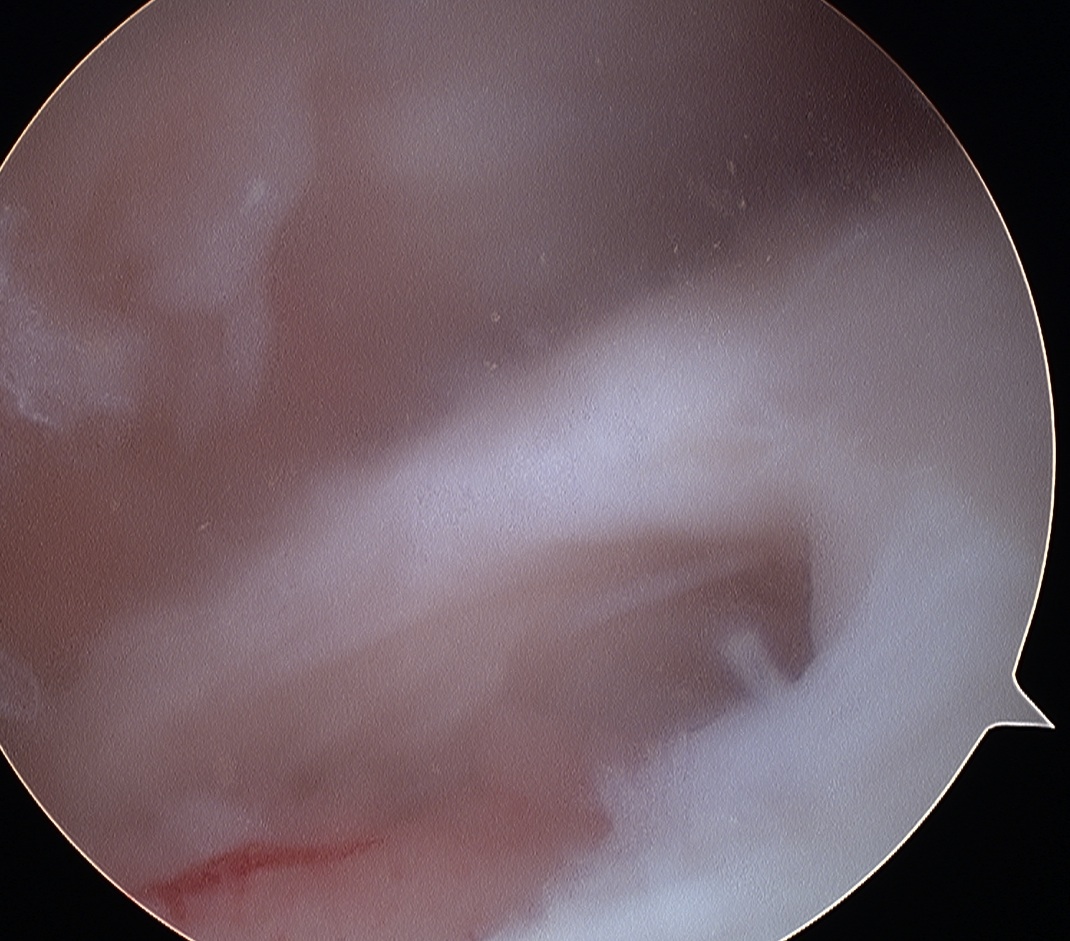

Partial thickness tear (PTT)

- incomplete

- bursal or articular sided